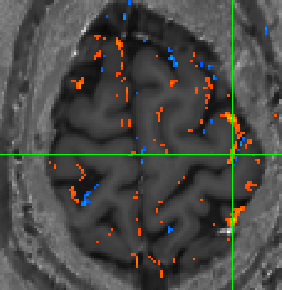

- Nils Nothnagel, Andrew Morgan, and Jozien Goense implemented a 3D-EPI sequence for layer-dependent VASO imaging.

- The first layer-fMRI VASO experiments were conducted early 2019.

-

0.6mm VASO during a visual paradigm acquired in Glasgow from Nils Nothnagel and Andrew Morgan